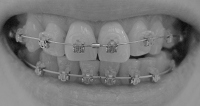

前回、最初の数日以来ほとんどガルバニーが出てなかったのですが、どうも2番目のワイヤーだったようです。となると、今回のは3番目のワイヤーだから、ガルバニー出現はないかも

慣れてきたのか単に素材の問題なのか、未だよくわかりませんが、無いならそれに越したことはないっ

だったら嬉しいな~。慣れてきたのか単に素材の問題なのか、未だよくわかりませんが、無いならそれに越したことはないっ